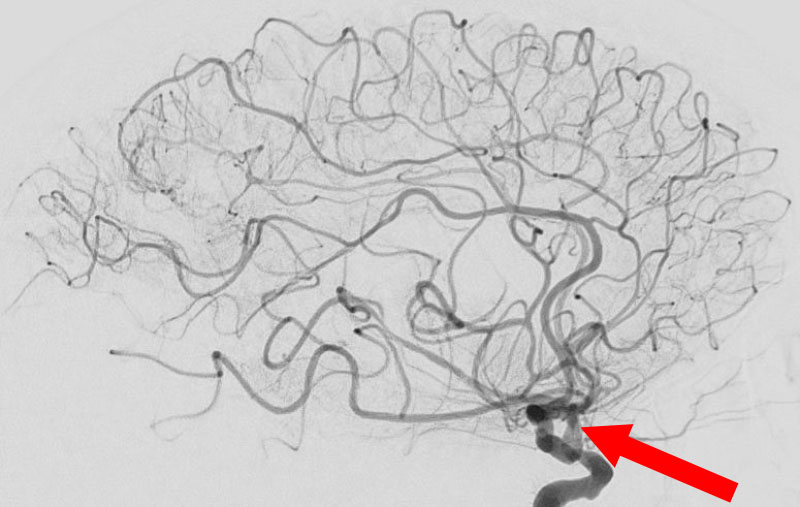

'25年10月

くも膜下出血

前交通動脈瘤破裂

60代

救急外来

No.1588 手術前

No.1588 手術中

No.1588 手術後